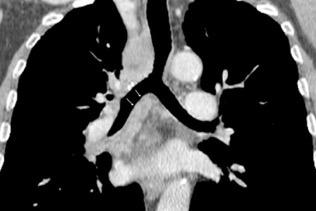

Síntomas y signos que se producen con la obstrucción total o parcial de la vena cava superior

Causas Malignas +/- 90-95%

Ca. Broncogénico (80-85%)

Linfoma No Hodgkin (15%)

Catéteres, shunts y marcapasos…23%

T. Mediastínico. Bocio

Fibrosis Idiopática

Tb, Histoplasmosis, Actinomicosis, Sarcoidosis

Carcinoma microcítico con síndrome de VCS

Grupos:

1. Obstrucción por encima de la V Ácigos. (La sangre llega al corazón a través de ella)

2. Obstrucción con participación de la V. Ácigos. (La sangre utiliza otras alternativas para llegar al corazón vía VCI).

Participación de la V. Ácigos como vía principal para llegar a la VCI.

Visible: 88%